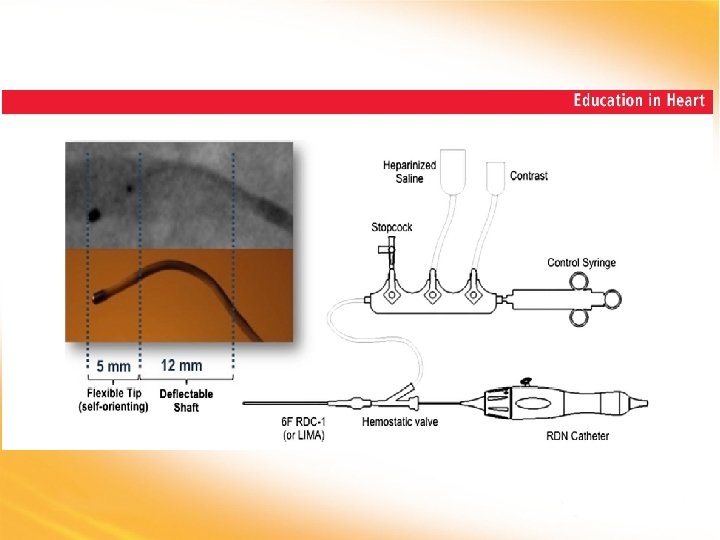

Current Symplicity™ Renal Denervation System • Ease of catheter flexibility and maneuverability • Responsiveness • Handle controls • 6 F guide cath compatible • Specifically designed for renal anatomy • • Fully automated generator Built-in safety algorithms Low-power Straightforward user interface The Symplicity system is not approved for sale in the US. It is an investigational device, limited by Federal (or United States) law to investigational use in the US.

Current Symplicity™ Renal Denervation System • Ease of catheter flexibility and maneuverability • Responsiveness • Handle controls • 6 F guide cath compatible • Specifically designed for renal anatomy • • Fully automated generator Built-in safety algorithms Low-power Straightforward user interface The Symplicity system is not approved for sale in the US. It is an investigational device, limited by Federal (or United States) law to investigational use in the US.